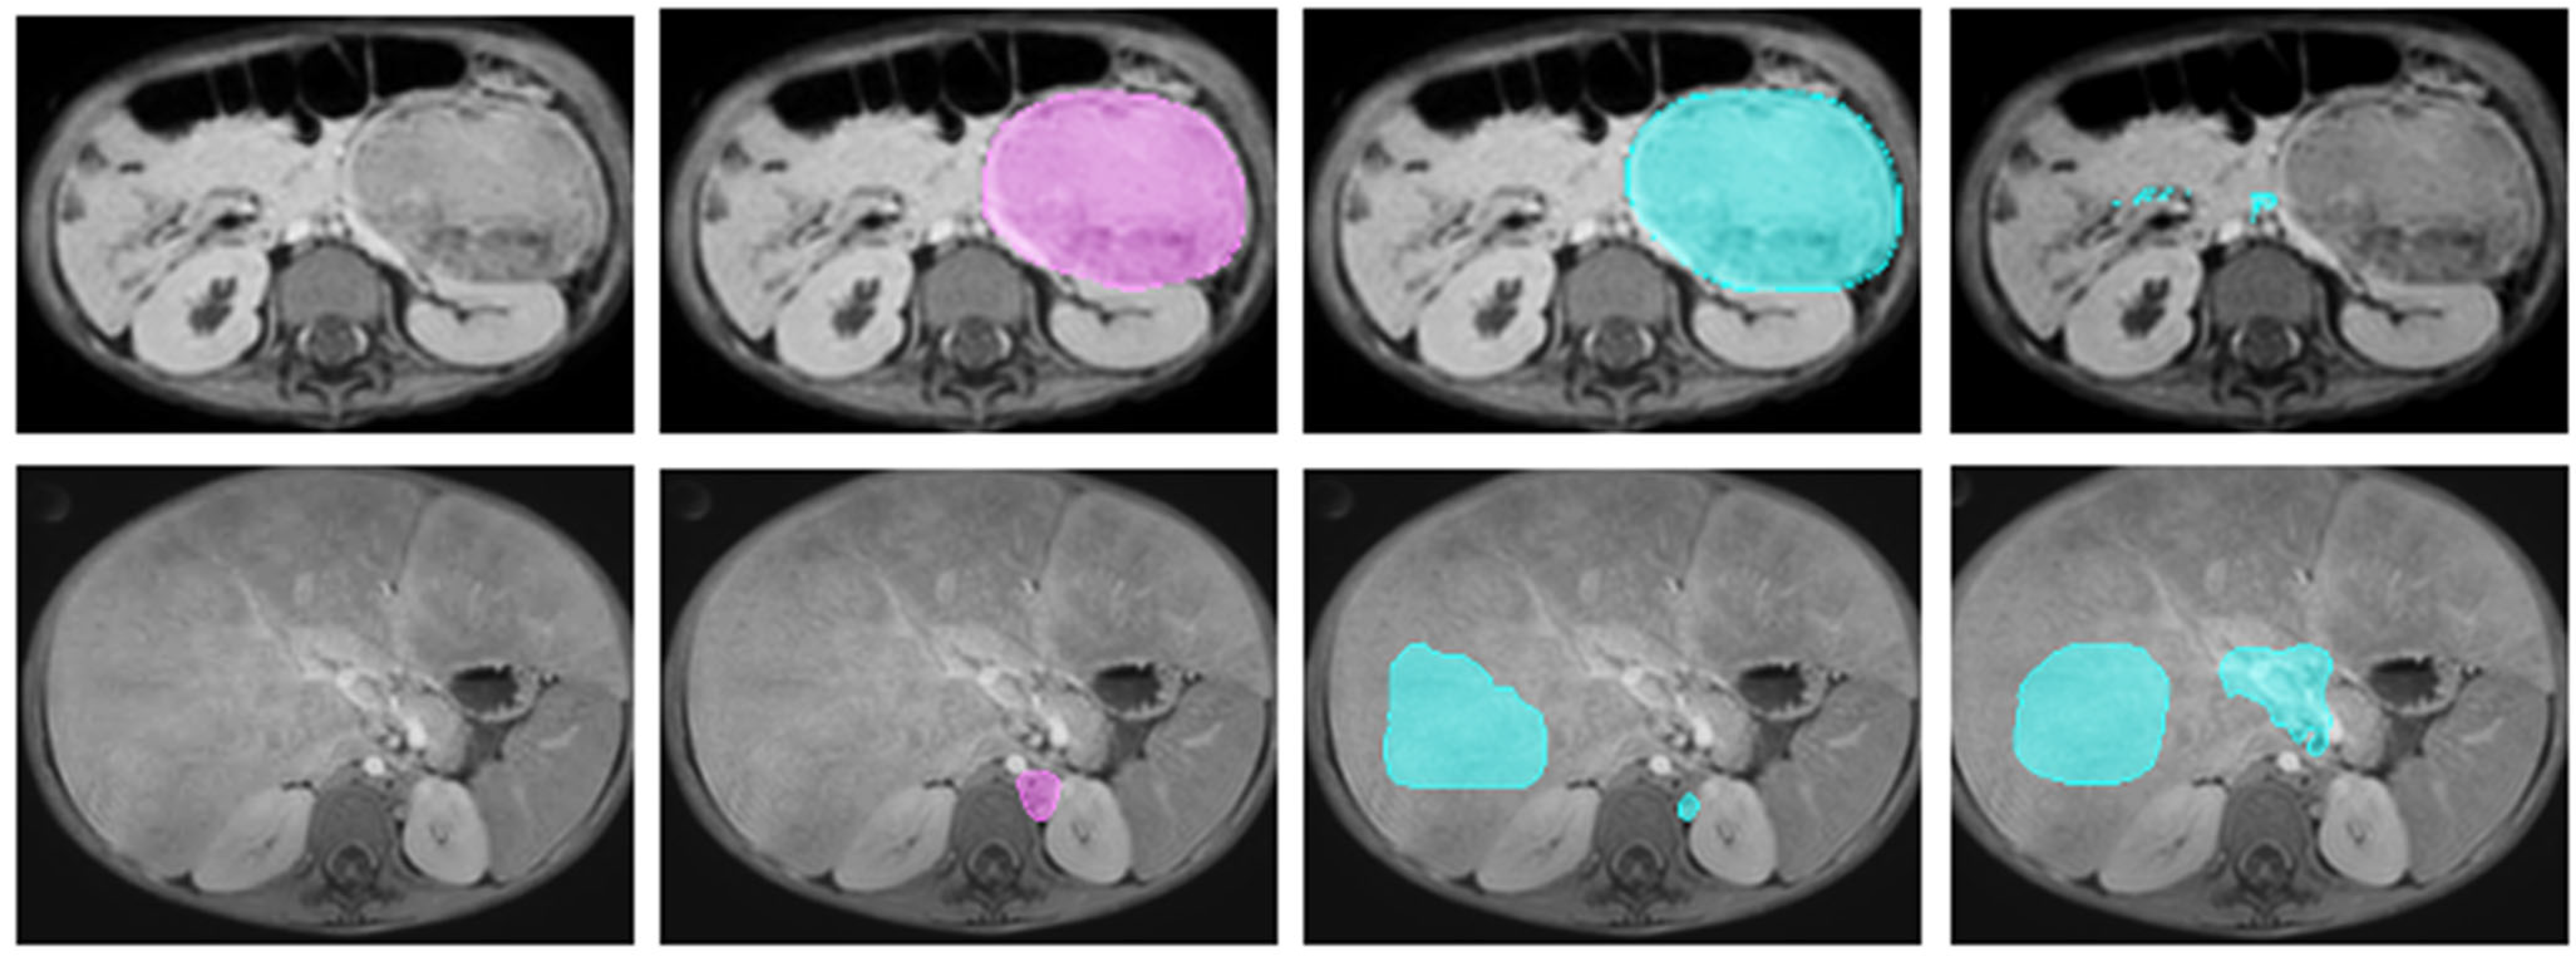

2.2.3. Manual Annotation

- Veiga-Canuto, D.; Cerdà-Alberich, L.; Sangüesa Nebot, C.; Martínez de las Heras, B.; Pötschger, U.; Gabelloni, M.; Carot Sierra, J.M.; Taschner-Mandl, S.; Düster, V.; Cañete, A.; et al. Comparative Multicentric Evaluation of Inter-Observer Variability in Manual and Automatic Segmentation of Neuroblastic Tumors in Magnetic Resonance Images. Cancers 2022, 14, 3648. [Google Scholar] [CrossRef] [PubMed]

- Veiga-Canuto, D.; Cerdà-Alberich, L.; Jiménez-Pastor, A.; Carot Sierra, J.M.; Gomis-Maya, A.; Sangüesa-Nebot, C.; Fernández-Patón, M.; Martínez de Las Heras, B.; Taschner-Mandl, S.; Düster, V.; et al. Independent Validation of a Deep Learning nnU-Net Tool for Neuroblastoma Detection and Segmentation in MR Images. Cancers 2023, 15, 1622. [Google Scholar] [CrossRef] [PubMed]